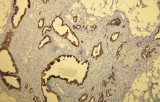

A imunohistoquímica (IHQ) com anticorpos primários CE/IVD é essencial para o diagnóstico e classificação precisos de malignidades ginecológicas e mamárias. Estes anticorpos permitem a deteção precisa de marcadores tumorais e proteínas celulares, apoiando o diagnóstico diferencial e guiando estratégias terapêuticas personalizadas.

Estudos recentes destacam o valor diagnóstico das proteínas do complexo SWI/SNF, particularmente ARID1B, na identificação de malignidades ginecológicas desdiferenciadas e indiferenciadas – tumores agressivos com mau prognóstico. A IHQ de ARID1B oferece elevada especificidade e está cada vez mais integrada em painéis diagnósticos para melhorar a precisão. Painéis com marcadores adicionais também apoiam a diferenciação de sarcomas uterinos, aumentando a exatidão diagnóstica. Evidência emergente sugere que ARID1B pode representar um alvo terapêutico potencial no carcinoma ovárico de células claras, embora as aplicações clínicas permaneçam em fase investigacional.

Anticorpos primários contra recetor de estrogénio (ER), recetor de progesterona (PR), HER2 e Ki-67 continuam a ser a pedra angular da classificação e decisões terapêuticas no cancro da mama. Estes anticorpos estão validados clinicamente e marcados CE/IVD para garantir deteção fiável e reproduzível de biomarcadores – crucial para orientar terapia hormonal e estratégias de tratamento direcionado.